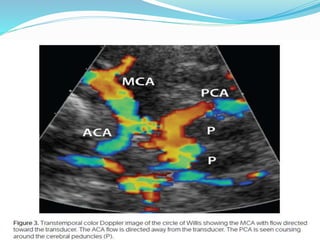

Trans-temporal insonation

 A red color signal (toward the probe) between 40 and

65mm - ipsilateral MCA.

 A blue signal between 65 and 80 mm - ipsilateral ACA.

 A red signal beyond 80 mm - contralateral A1 ACA

 A bidirectional signal obtained at 60-70 mm represents

ICA bifurcation.

 The ultrasound probe is slowly oriented posteriorly by 10

to 30 degrees.

 Usually there is a flow gap followed by flow signals from

the PCA.

 Flow signals directed toward the probe - P1 PCA

 Away from the flow - P2 segment of the PCA

 Both segments are visualized at depths of 55-70 mm.

Trans-temporal insonation  Ared color signal (toward the probe) between 40 and 65mm - ipsilateral MCA.  A blue signal between 65 and 80 mm - ipsilateral ACA.  A red signal beyond 80 mm - contralateral A1 ACA  A bidirectional signal obtained at 60-70 mm represents ICA bifurcation.

 The ultrasoundprobe is slowly oriented posteriorly by 10 to 30 degrees.  Usually there is a flow gap followed by flow signals from the PCA.  Flow signals directed toward the probe - P1 PCA  Away from the flow - P2 segment of the PCA  Both segments are visualized at depths of 55-70 mm.  An absence of the flow gap while moving the transducer posteriorly after MCA/ ACA evaluation - PCOM.